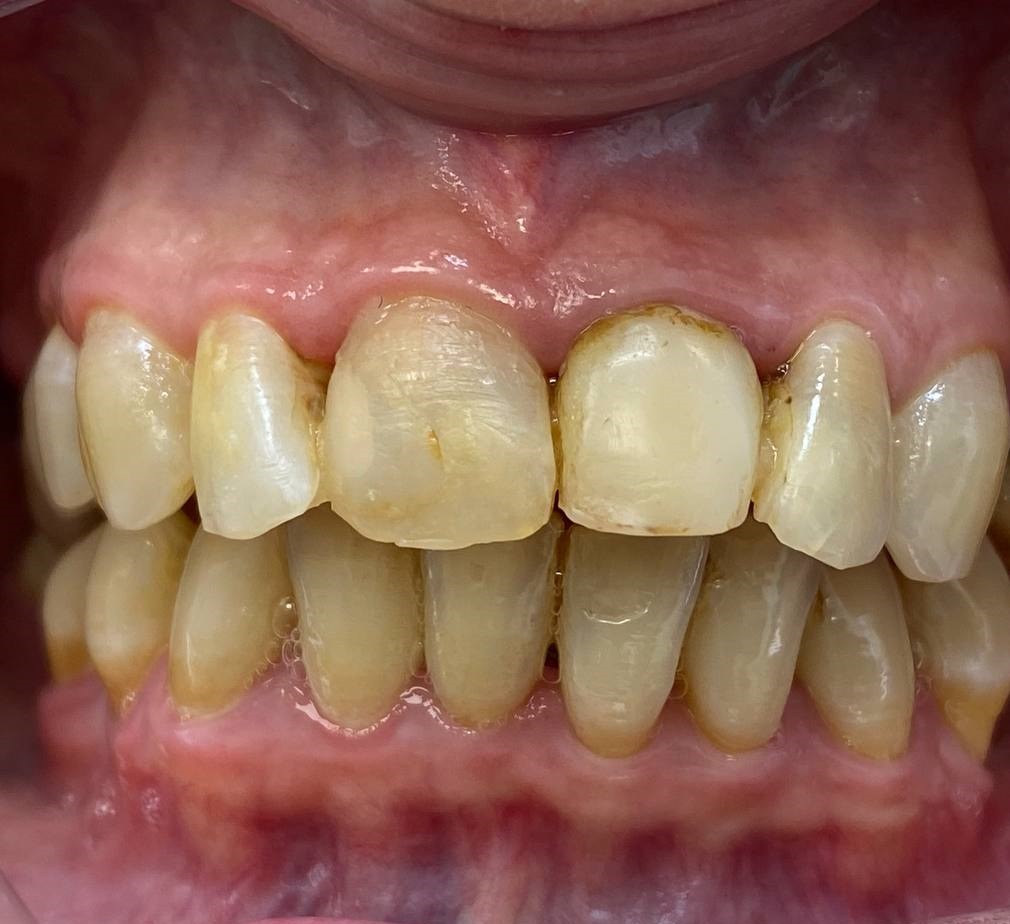

Проблема

У пациента отмечалось опущение десны, выраженный налёт и эстетически неудовлетворительный вид верхних передних зубов.

Решение

После лечения: Установлены 4 коронки на передние верхние зубы, выполнено поднятие десны — улыбка стала более ровной, светлой и аккуратной.